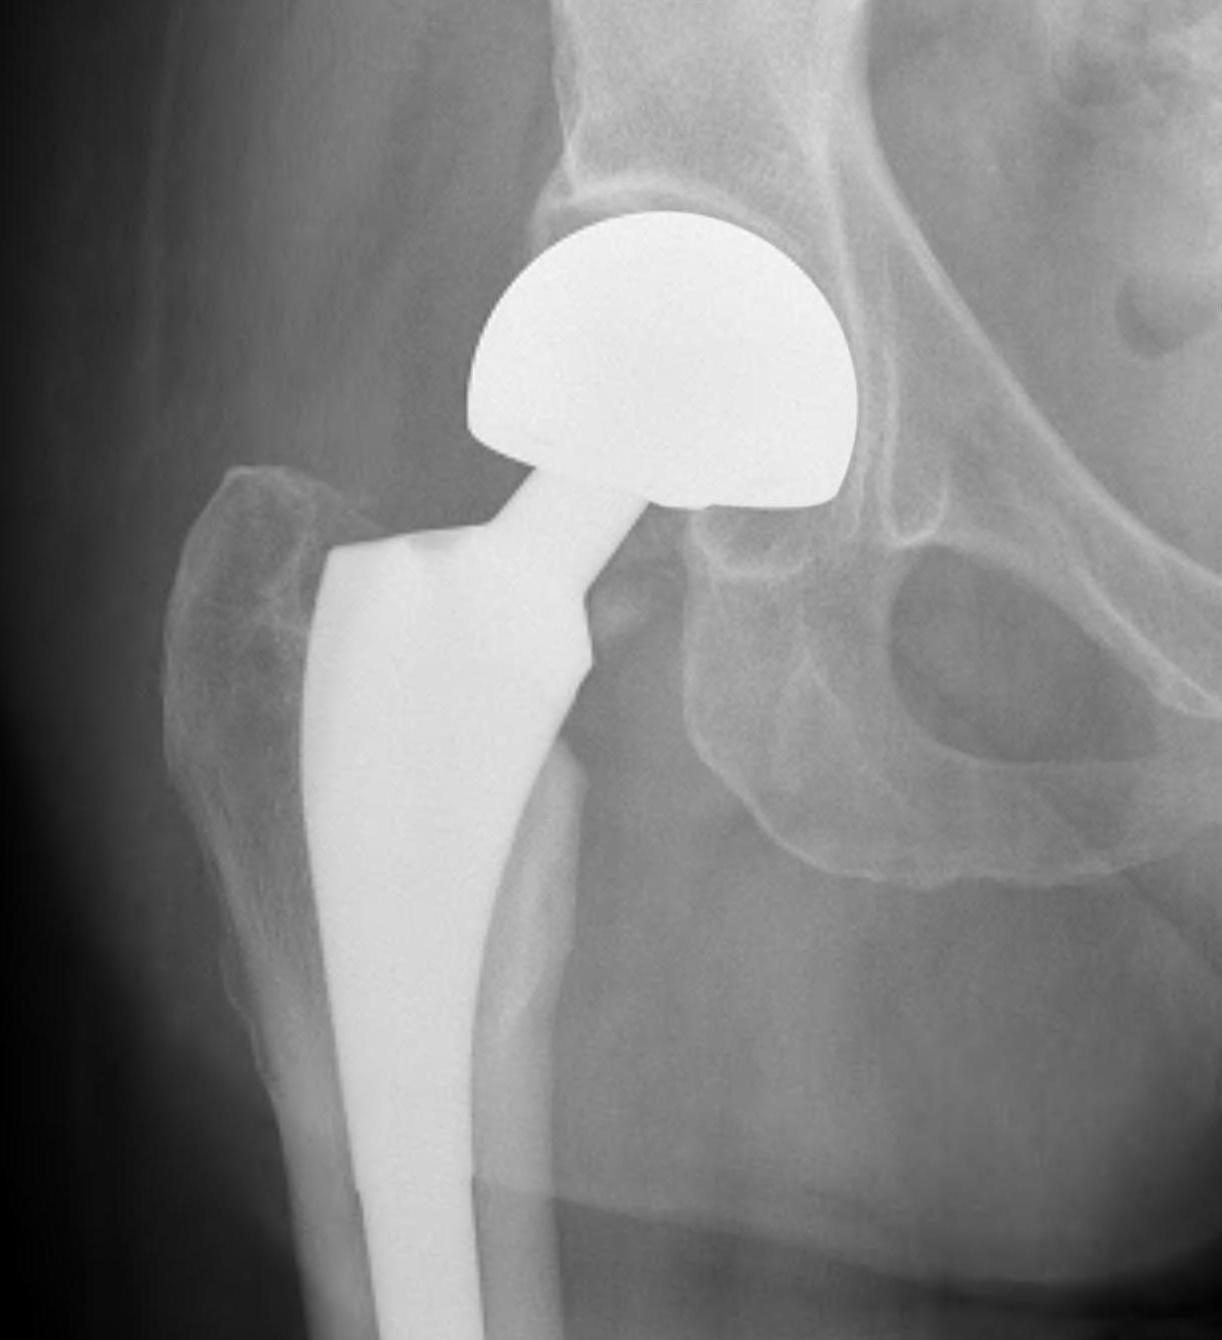

Cemented unipolar hemiathroplasty Uncemented bipolar hemiarthroplasty

Cement

- minimizes fracture risk in osteoporotic patients

- reduced risk thigh pain

- slightly increased cardiac risk with cement